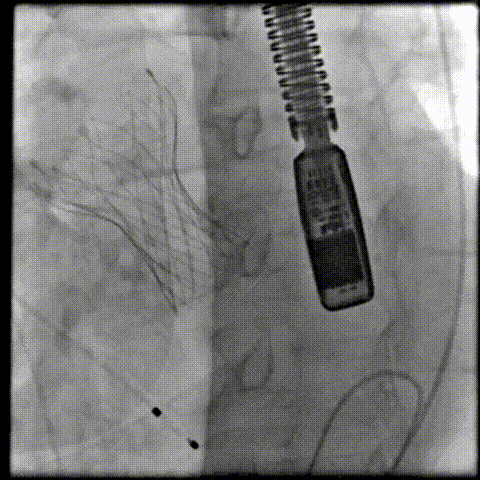

此身凌云摘荣耀,意气扬帆向新章。12月1日,正值“2024亚洲心脏瓣膜中国论坛”盛大召开之际,在中国研究型医院学会心脏瓣膜病学专业委员会主任委员、亚洲心脏瓣膜病学会中国部分主任委员刘立明教授、广西医科大学第一附属医院郑宝石教授、中国研究型医院学会心脏瓣膜病学会常委/秘书长、首都医科大学附属北京安贞医院张海波教授的支持下,TAVR实战复盘年终钻石赛重磅来袭。

大赛汇聚几十位国内心脏瓣膜领域的权威专家,借助实战复盘以及快问快答等多种形式全盘铺开。10位优秀的青年术者相聚于此,为最终的冠军头衔展开激烈角逐!

首都医科大学附属北京安贞医院张海波教授于开场致辞时着重提出,本届赛事成功突破了传统的赛事模式与框架,巧妙地将丰富多元且饶有趣味的元素融入其中。凭借这一活动,每位专家同道都能够在知识储备维度上获得实质性的增长与扩充,其学术视野的广度与深度也能够得到有效拓展。这对于经股TAVR技术在临床实践过程中提升精准性、保障高效性、巩固安全性给予了强有力的推动作用。